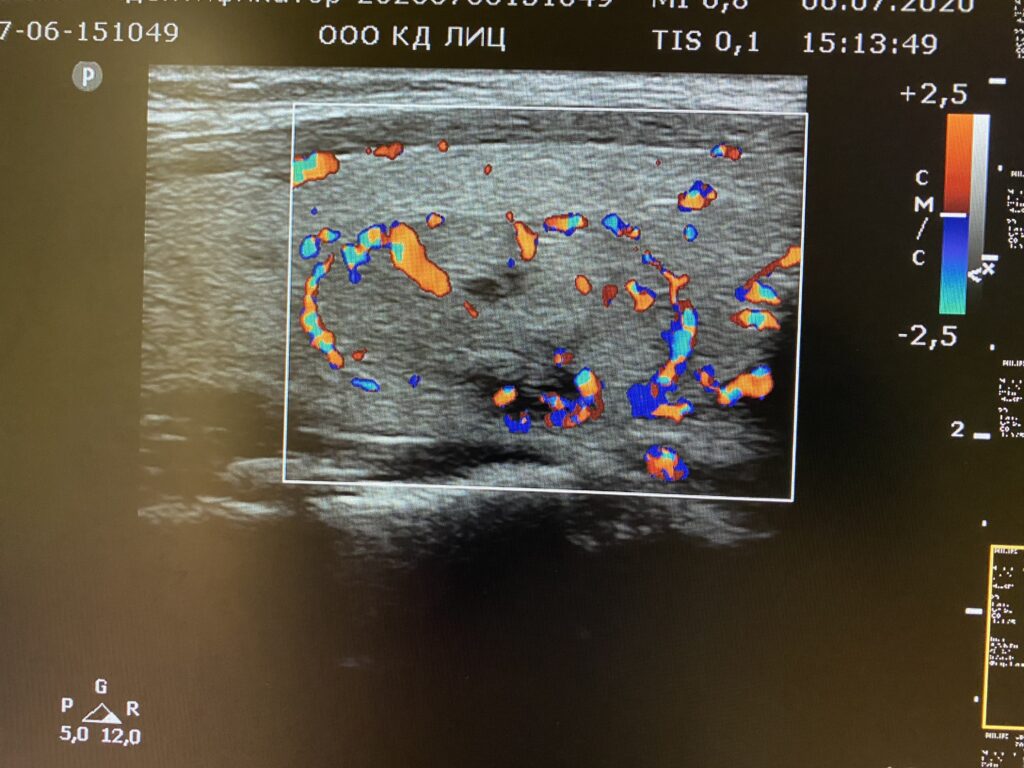

Мезентериальные лимфатические узлы: УЗИ и диагностика